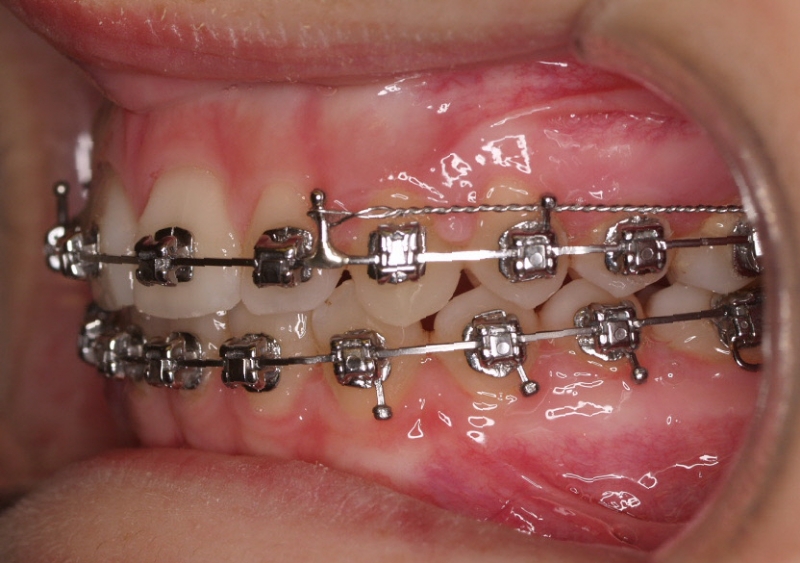

Clase II paciente 15 años

La paciente O.O. acude a nuestra consulta por:

– Canino 13 e incisivo lateral 42 en posición ectópica.

– Canino 23 incluido.

Con lo que decide realizarse un tratamiento de ortodoncia de duración de 24 meses con brackets damon Q.